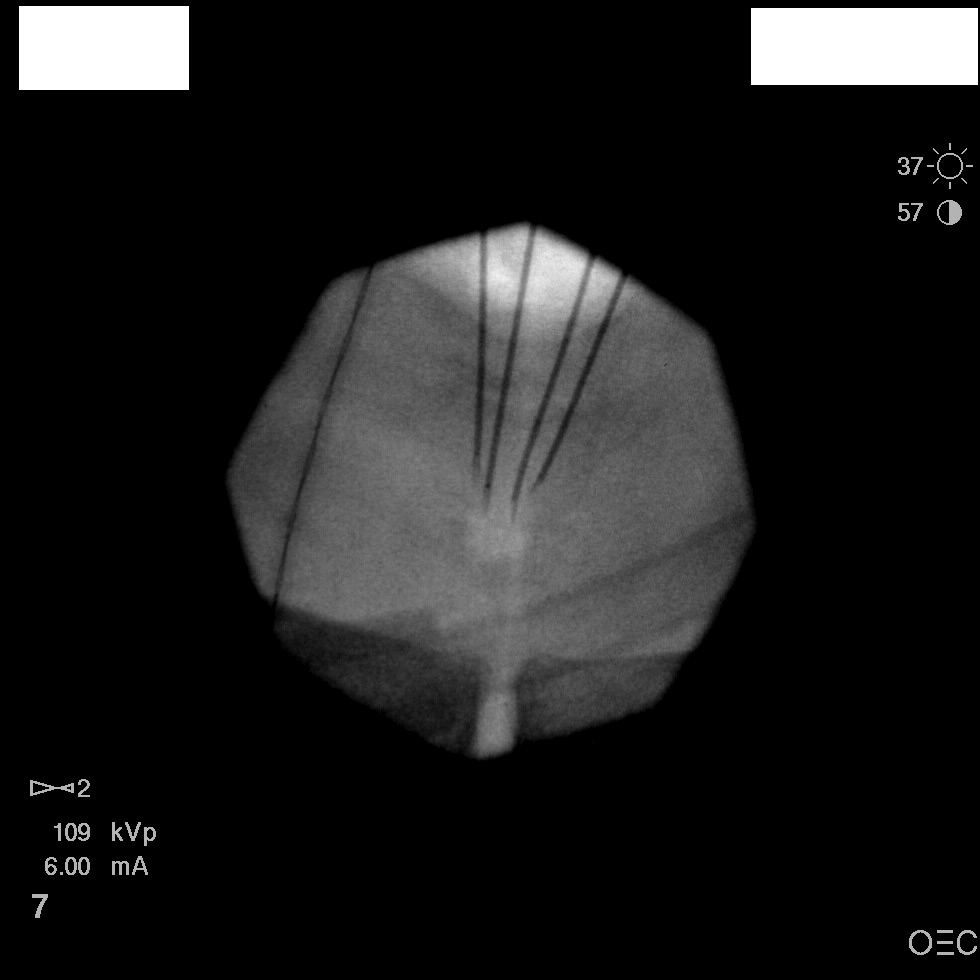

I have a patient with several months of coccyx pain. Worse with sitting, TTP over coccyx. Otherwise normal exam. No trauma, but she has an anteriorly displaced coccyx. Failed NSAIDs and no one around me does good pelvic floor PT. I scheduled her for ganglion impar injection, but her insurance won't pay for it. They wouldn't even let me to a peer-to-peer... they just straight up said they won't cover it. Any other treatment options? I don't want to send her to a surgeon. Thanks.